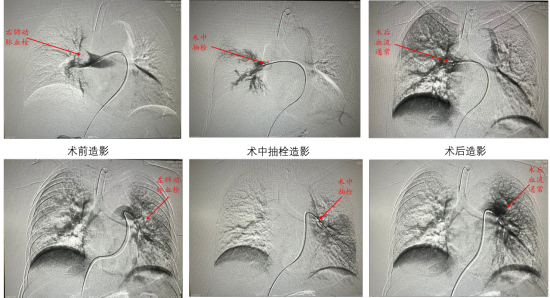

面对张大娘的病情,哈医大四院介入血管外科闫龑主任医师团队迅速接诊,结合患者病史及检查结果,判断其病情危急——肺栓塞作为致命性血管疾病,血栓堵塞肺动脉会导致肺部血液循环障碍,若延误治疗可能引发呼吸衰竭、休克甚至猝死。考虑到患者经前期治疗效果不佳,团队果断制定个性化介入治疗方案,采用微创介入技术精准清除肺动脉内血栓,同时辅以抗凝治疗预防血栓复发。

手术过程中,闫龑主任医师凭借精湛医术和丰富经验,全程精准操作,成功清除堵塞血管的血栓,恢复肺动脉血流通畅。术后患者呼吸困难症状迅速缓解,生命体征逐渐平稳,目前正在康复中,对治疗效果十分满意。(完)